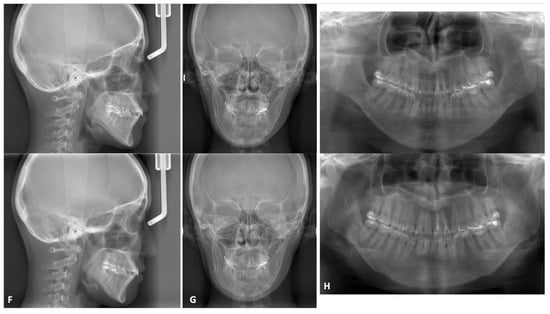

3.2.2. Mandibular Osteotomies